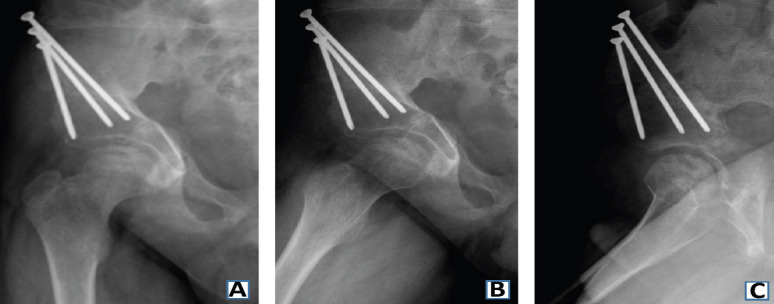

Case report: In this report, we present the case of an 8-year-old Hispanic male who presented with bilateral hip pain unresponsive to conservative treatment and initially managed with the presumptive diagnosis of LCP disease. Due to his persistent hip pain and no improvement on follow-up X-rays and magnetic resonance imaging (MRI), the patient was referred to our hip preservation clinic for further work-up and management recommendations. MRI revealed bilateral OCD lesions of the femoral head secondary to developmental hip dysplasia. The patient underwent bilateral triple PAO for correction of the patient's bilateral hip dysplasia, which resulted in the proper resolution of the femoral head lesions on imaging and eventually resolved the patient's hip pain.